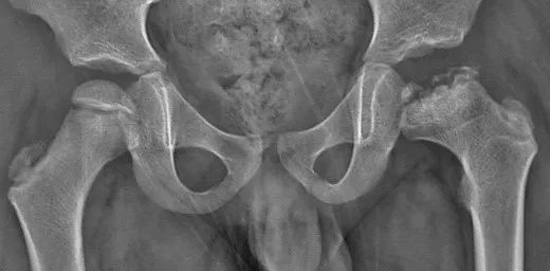

Perthes病碎裂期表现

Perthes病愈合期的残留畸形:扁平膨大的股骨头、股骨颈短、大粗隆高位、髋臼发育不良